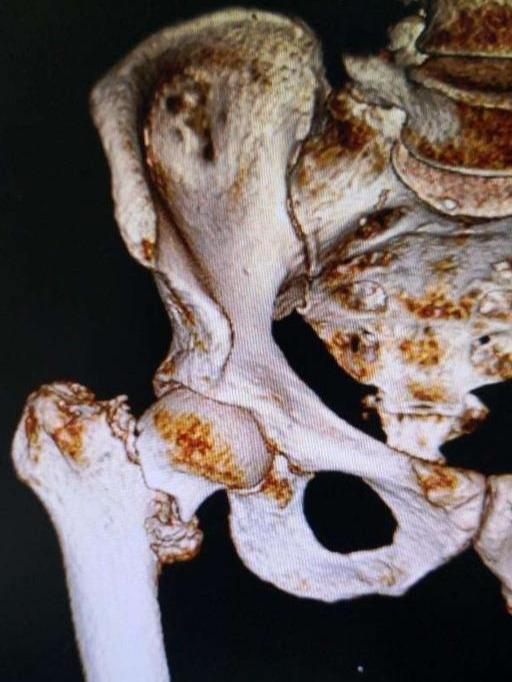

老人的骨折,特别是脊柱骨折,髋关节骨折,对老人的伤害是最严重的!

这些并发症的存在,所以髋部骨折,以前被叫做“临终性骨折”或者“人生的最后一次骨折”。腰椎骨折和下肢的其他骨折影响小一点。但急性损伤的伤害,对身体的打击,脂肪栓塞,出血等等,也是很严重的,老人家的身体恢复能力不够强,很多就一蹶不振了。加上没有科学的护理,导致很多老人家熬不过这一关。就算熬过了这一关,身体状况也大打折扣,后面发生其他并发症的可能性也大了很多。寿命受到影响也很正常!!

现代骨科的发展和护理水平的提高,老百姓经济水平的上升,交通的便利,大家观念的改变,让很多老人得到及时的救治,挽救了无数的老人。特别是人工关节和微创技术的日新月异,快速康复理念的普及,更是骨折老人的福音。通过手术治疗,绝大多数老人得到康复,不过,个别还是还是出现了并发症,导致无法康复或者死亡,只是几率比以前已经大大的降低了,相信随着医疗护理水平的提升,会有越来越多的老人得到正确的治疗。